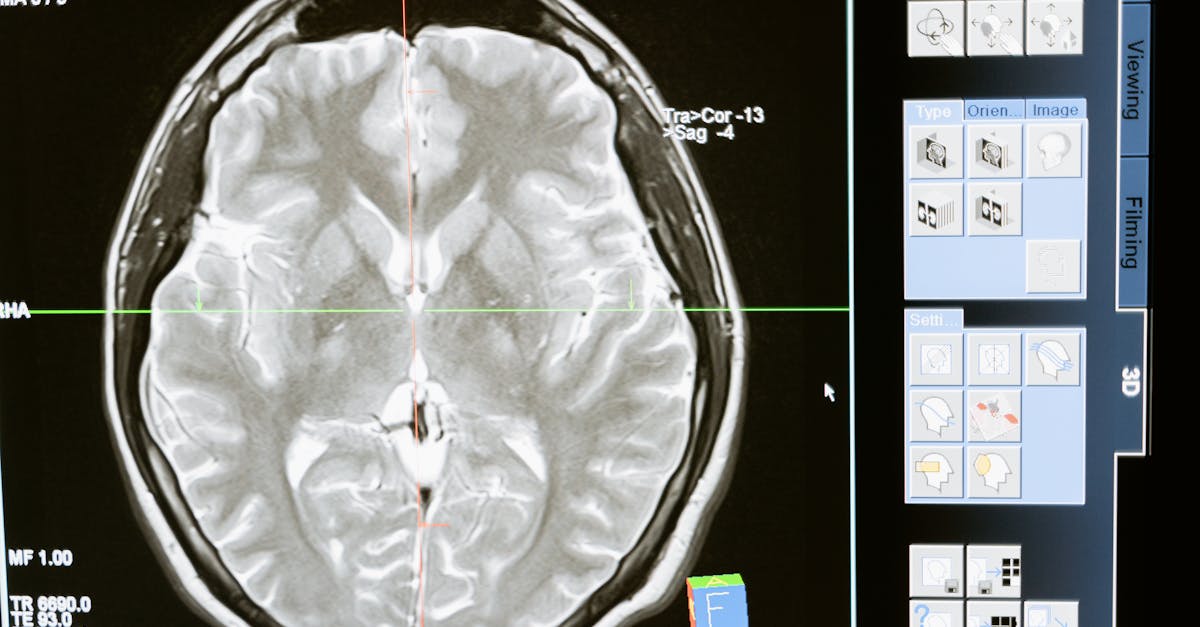

Nuclear medicine imaging is a powerful diagnostic tool that allows healthcare professionals to visualize the body's anatomy and function by using small amounts of radioactive materials. One common technique within nuclear medicine imaging is Single Photon Emission Computed Tomography (SPECT). SPECT provides detailed three-dimensional images of the body's organs and tissues by detecting the gamma rays emitted from the radioactive tracer.

Another emerging trend in nuclear medicine imaging is the use of Positron Emission Tomography (PET) scans. PET scans are particularly useful in detecting diseases at an early stage when treatments are most effective. By injecting a small amount of radioactive material into the body, PET scans can help identify cellular-level changes in organs and tissues, making it a valuable tool in oncology, cardiology, and neurology. The combination of detailed anatomical information from CT or MRI scans with functional information from PET scans has revolutionized the field of nuclear medicine imaging, allowing for more accurate diagnoses and targeted treatment plans.

Single Photon Emission Computed Tomography (SPECT) is a highly valuable imaging technique that aids in diagnosing various medical conditions. This imaging modality works by detecting gamma rays emitted by a radioactive tracer injected into the patient's bloodstream. SPECT provides detailed three-dimensional images of specific tissues or organs in the body, offering valuable insights into their functioning and potential abnormalities.

One of the key advantages of SPECT imaging is its ability to capture functional information, allowing healthcare professionals to assess organ function alongside structural details. This makes SPECT particularly useful in diagnosing conditions such as heart disease, brain disorders, and cancer. By combining functional and anatomical data, SPECT enables a comprehensive evaluation of the patient's health status, guiding treatment decisions and monitoring disease progression.